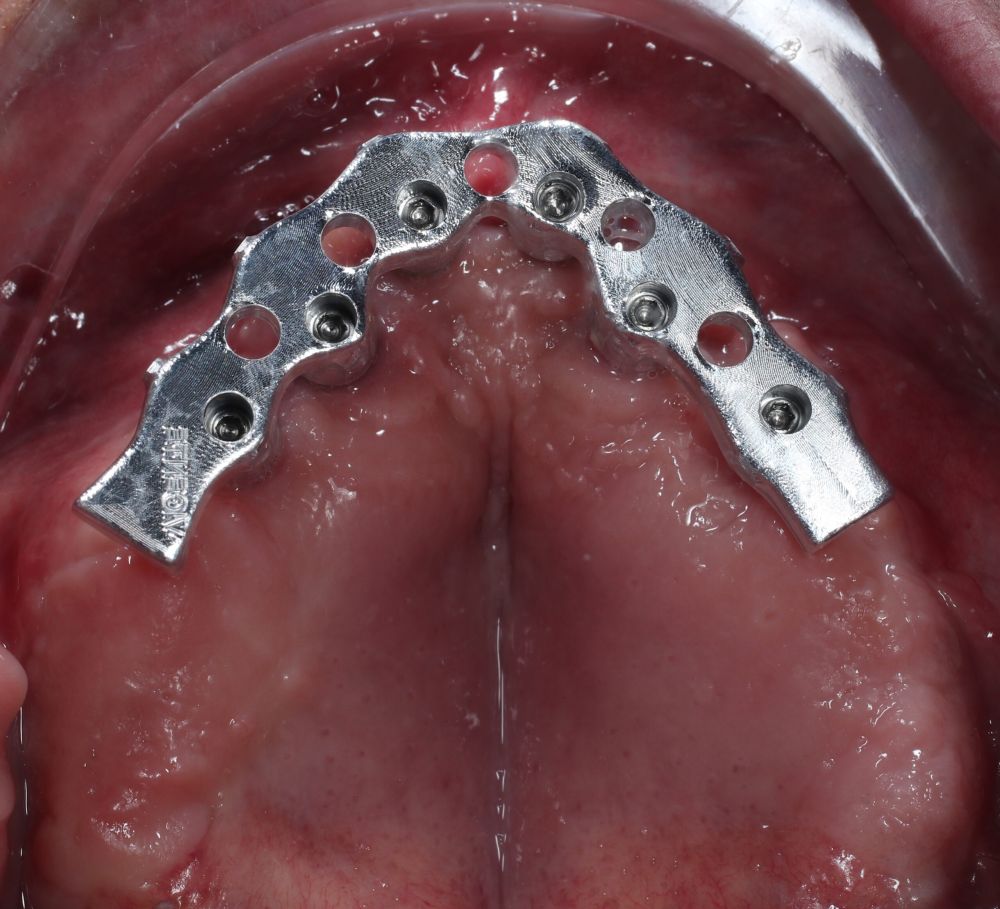

Clinical Case: A subperiosteal sintered titanium structure was fabricated with six transepithelial connections that were rehabilitated with an immediate implant supported fixed prosthesis made of PMMA. Two months later, a sintered chromium-cobalt framework with machined bases covered with acrylic resin teeth was fabricated as the final restoration. At one year follow-up, the case remains stable.

Subperiosteal implants (SI) were developed in Sweden in the early 1940´s. The SI consisted of a custom-made implant, inserted under the periosteum and fixed with screws and the mucous tissue that covered it3,4. They were manufactured in chromium-cobalt or titanium alloys and were rehabilitated by transmucous pillars that emerged in the oral cavity5. Although they were used for years in cases of maxilla atrophies, they were replaced by endoosseous implants designed by Branemark6. This was due to its complex manufacturing. It was necessary to take an impression of the residual bone ridge, which was sent to the laboratory for the structure design, with the consequent imbalances since they were not very stable models. In this way, its placement in the patient was very difficult, and several complications could appear7,8. However, advances in the planning and manufacturing field with various materials have allowed these structures to be made digitally with an excellent predictability and fit, thus avoiding more complex surgeries9.